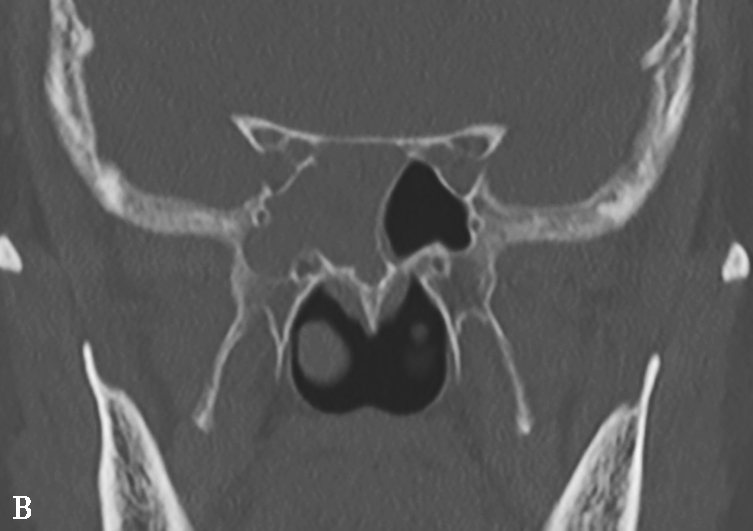

图1-3-30 鼻石症

A、B.横断面及冠状面CT骨窗,示左侧鼻腔底部不规则形高密度影,病变密度类似骨皮质

5.CT平扫表现

有核的鼻石核心为低密度影,周围环绕高密度影。无核鼻石表现为均匀高密度(图 1-3-30)。